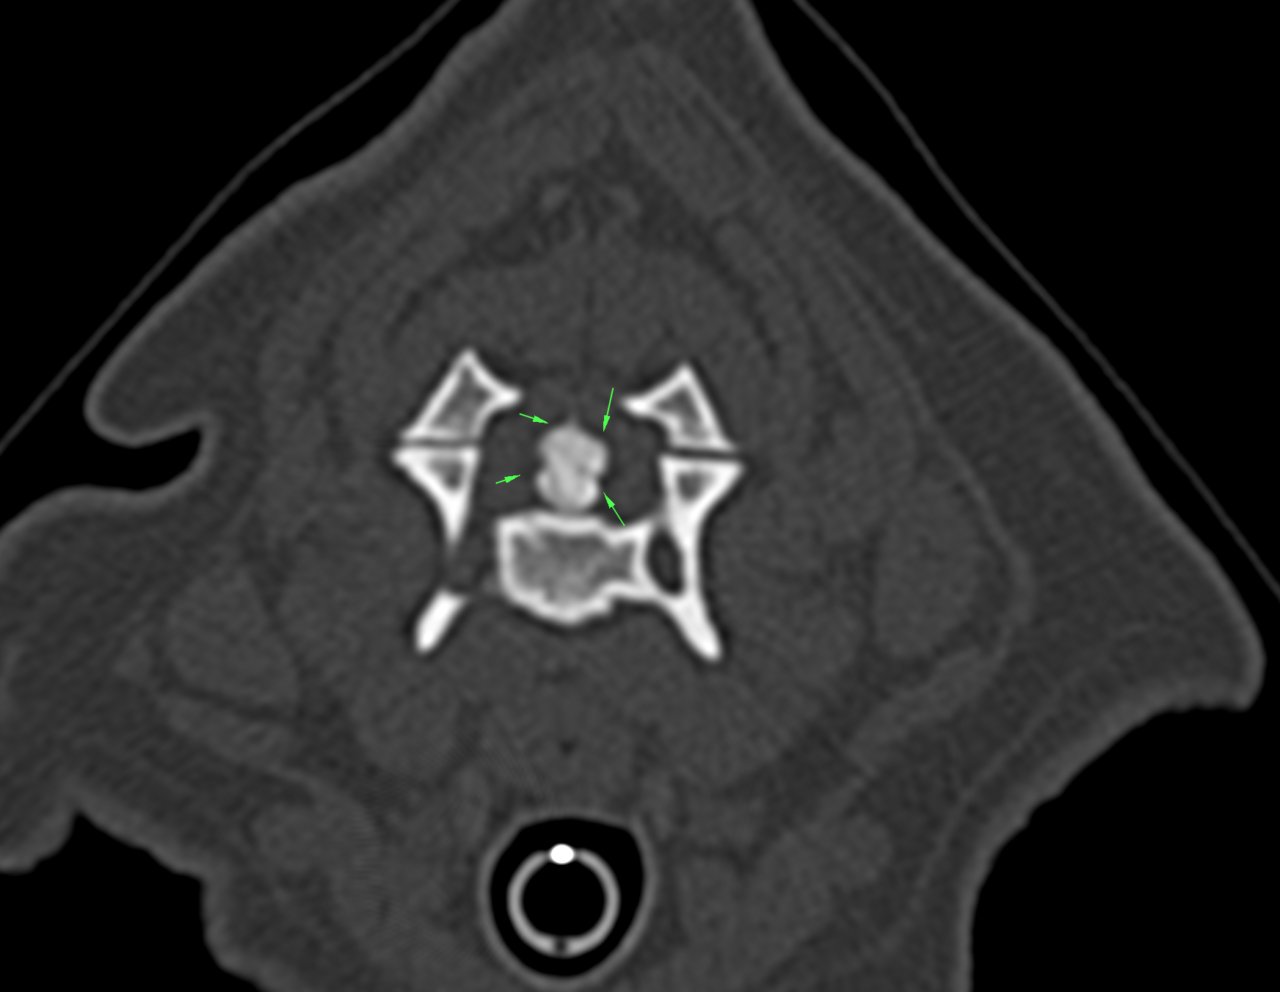

頸の痛みとふらつきを主訴にペキニーズさんが受診されました。CT/MRIで脊髄の状態を確認するとC3~C4に重度の脊髄圧迫病変が確認されました。Ventaral Slotで除圧術を行いました。数日は呼吸状態に留意しながら、回復を待ってリハビリテーションを検討します。

頸の痛みとふらつきを主訴にペキニーズさんが受診されました。CT/MRIで脊髄の状態を確認するとC3~C4に重度の脊髄圧迫病変が確認されました。Ventaral Slotで除圧術を行いました。数日は呼吸状態に留意しながら、回復を待ってリハビリテーションを検討します。